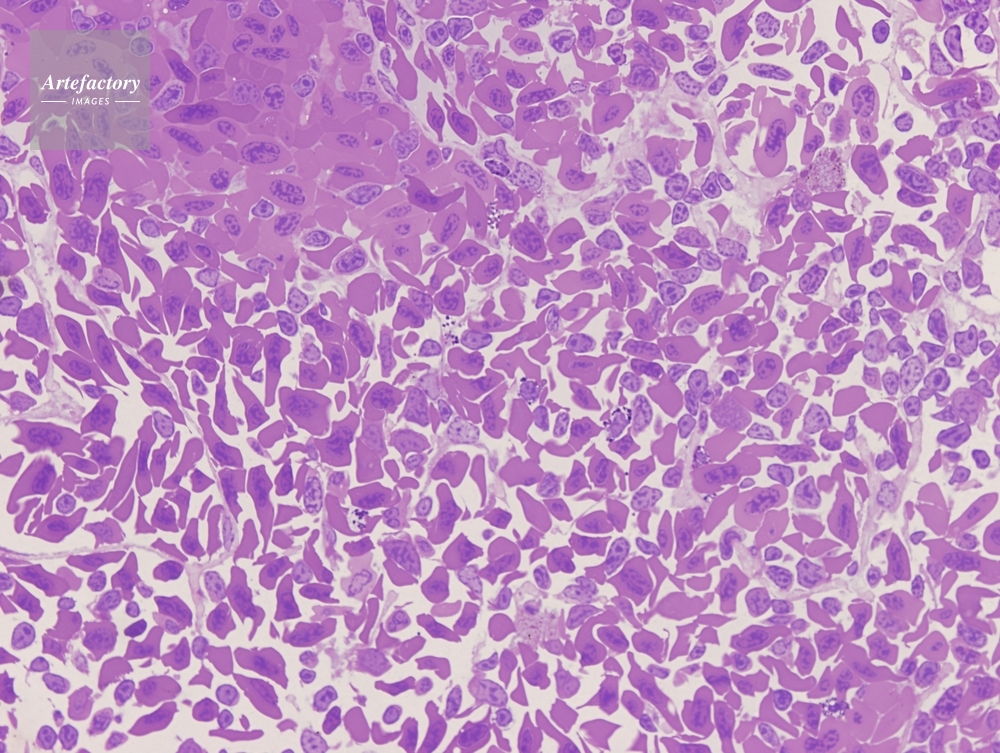

| 作品タイトル | イモリ 脾臓 | モデルリリース | なし | |

| 作家 | OLYMPUS CORPORATION Technolab | プロパティリリース | なし | |